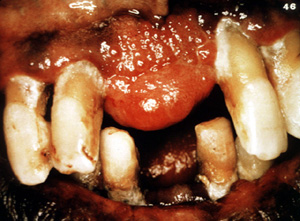

Este ejemplo típico se ulcera focalmente pero es asintomático. Este varón de 48 años de edad declaró que la lesión se había estado agrandando durante 5 años. Los dientes aparecen separados. Es frecuente  que estas lesiones pueden ser bastante agresivas y pueden cambiar de sitio a los dientes.

Esta gran lesión se extendió bien en lingual y cambió de sitio algunos de los dientes. Los granulomas periféricos lograrán un tamaño considerable sin tratamiento. La terapia es la biopsia por escisión . Puede ser necesario extender la cirugía  al hueso subyacente para eliminar la lesión. También se indica la eliminación de estímulos irritantes.